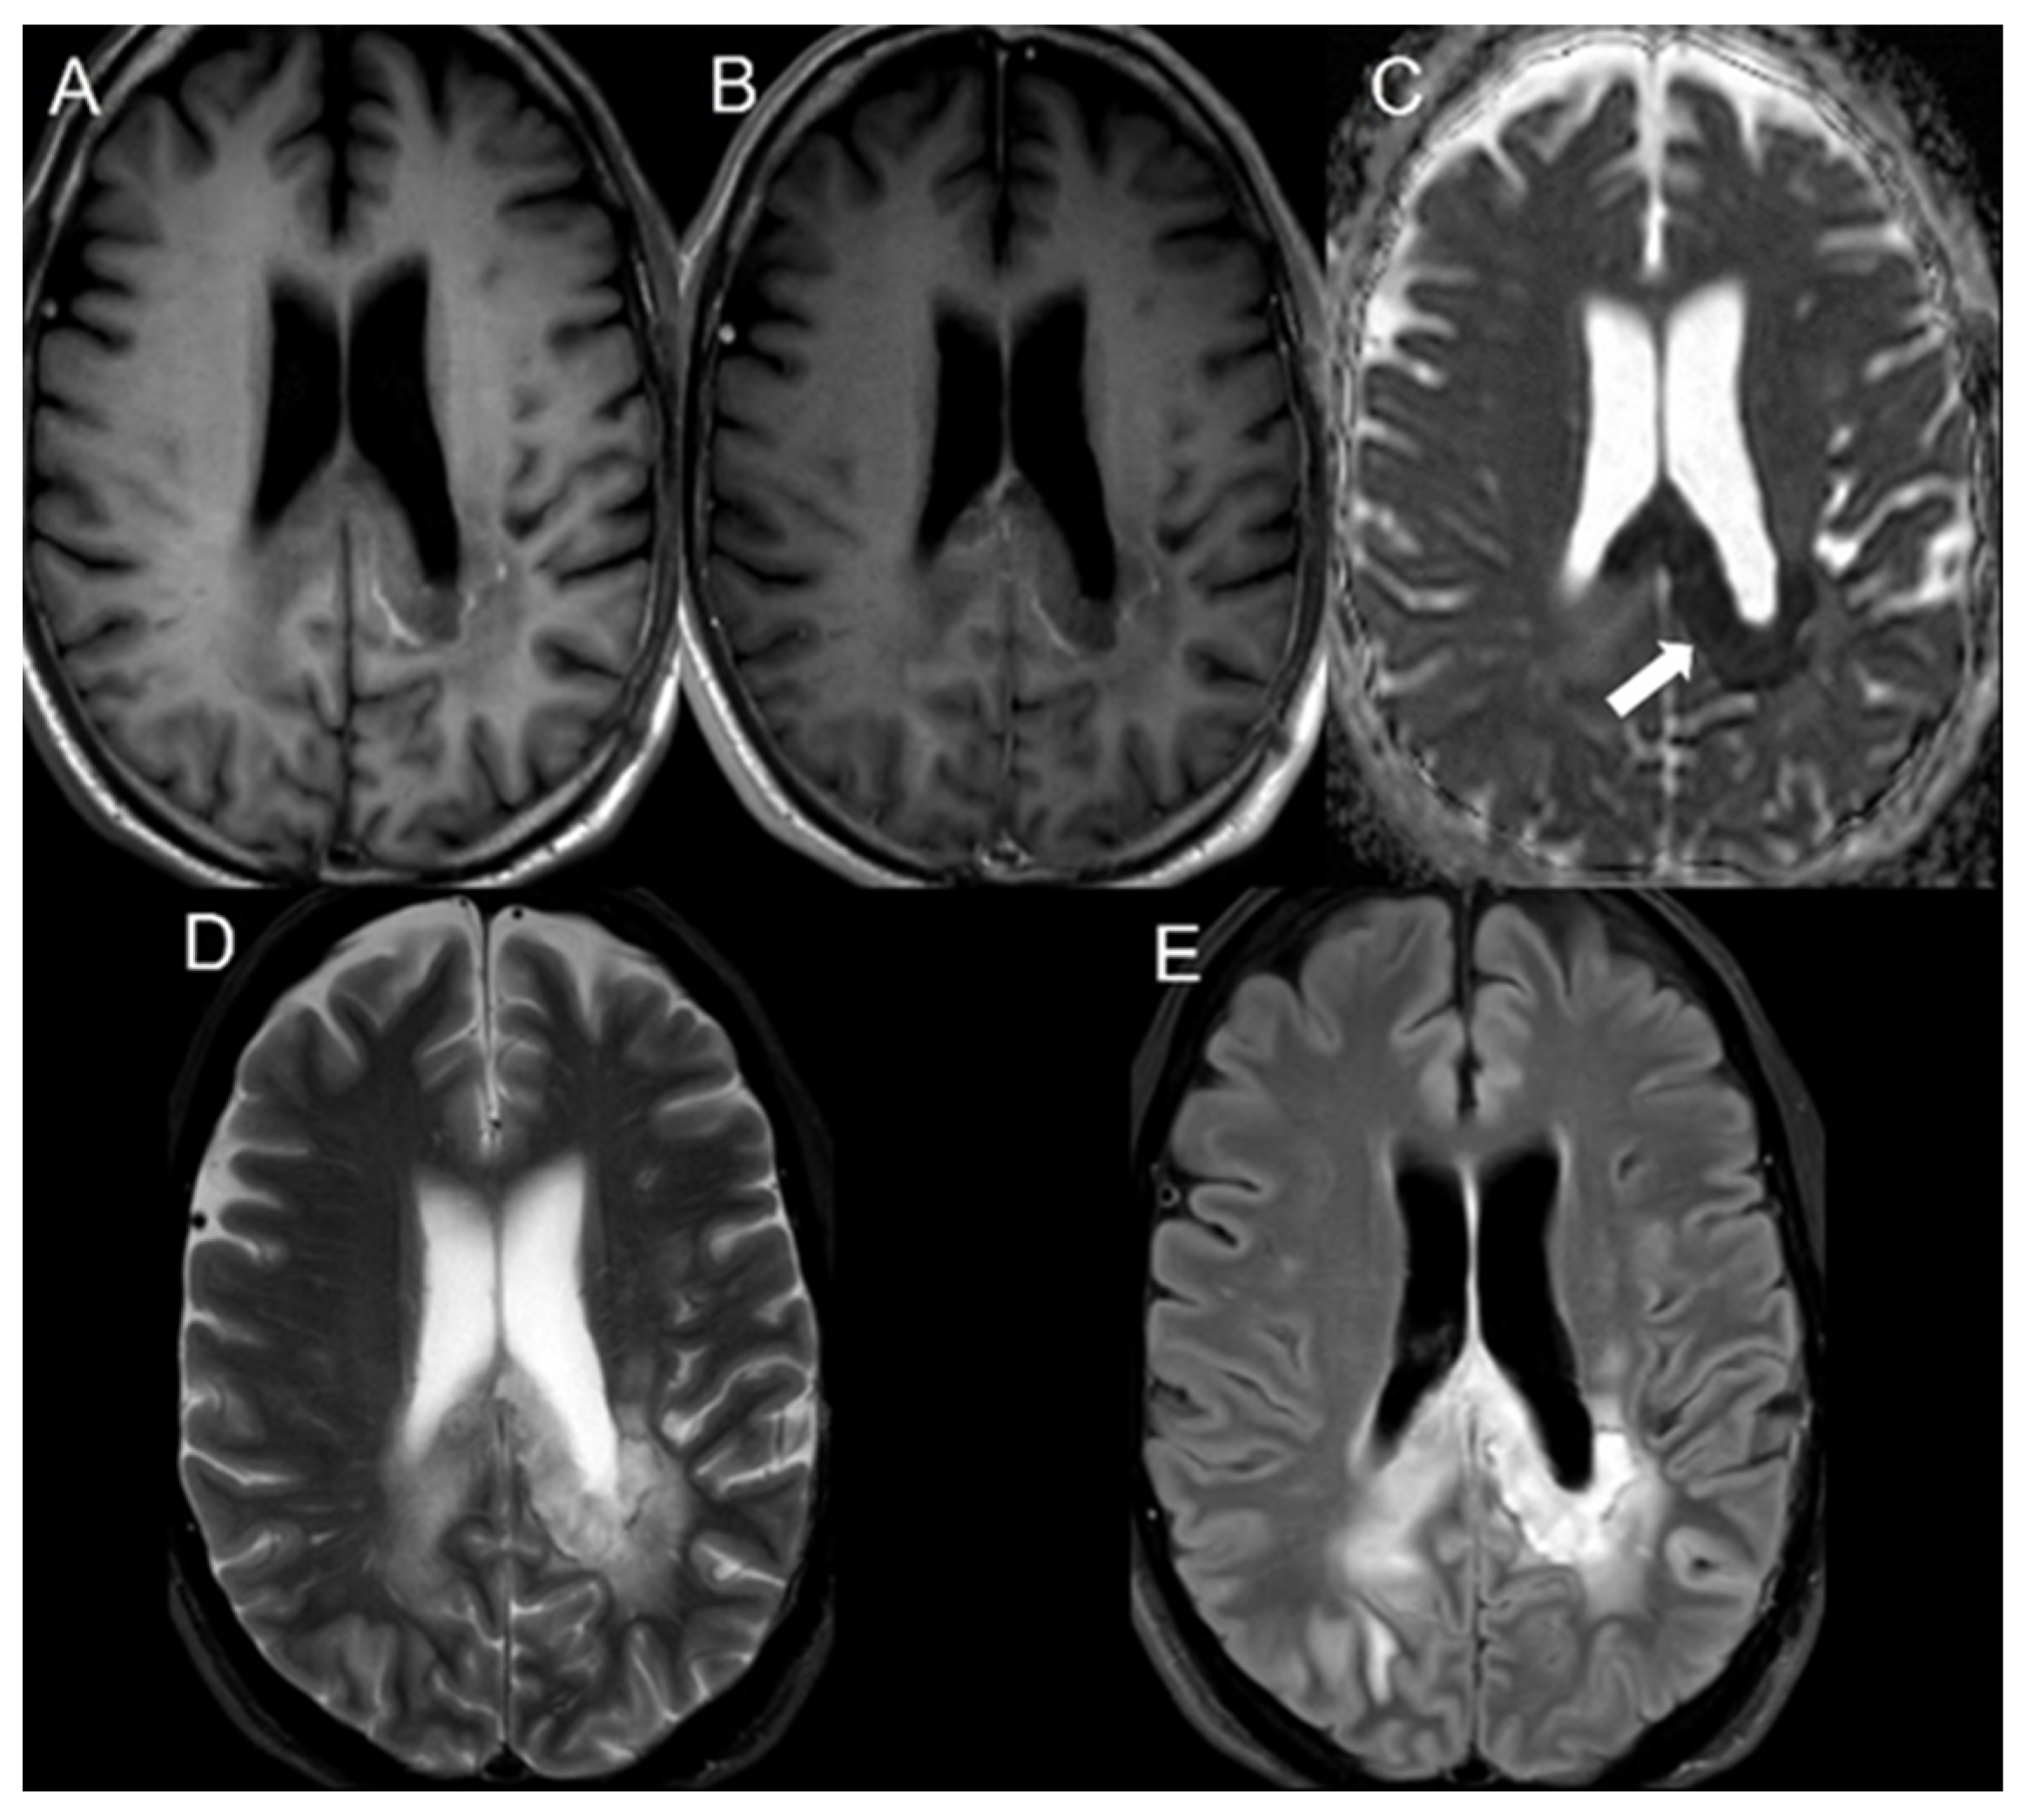

| Bevacizumab | 21 | 248.1 ± 67.2 | 647.2 ± 94.6 | <0.001 |

| Bevacizumab | 1.00 | N/A |

| Bevacizumab | 21 | 0.39 ± 0.10 |